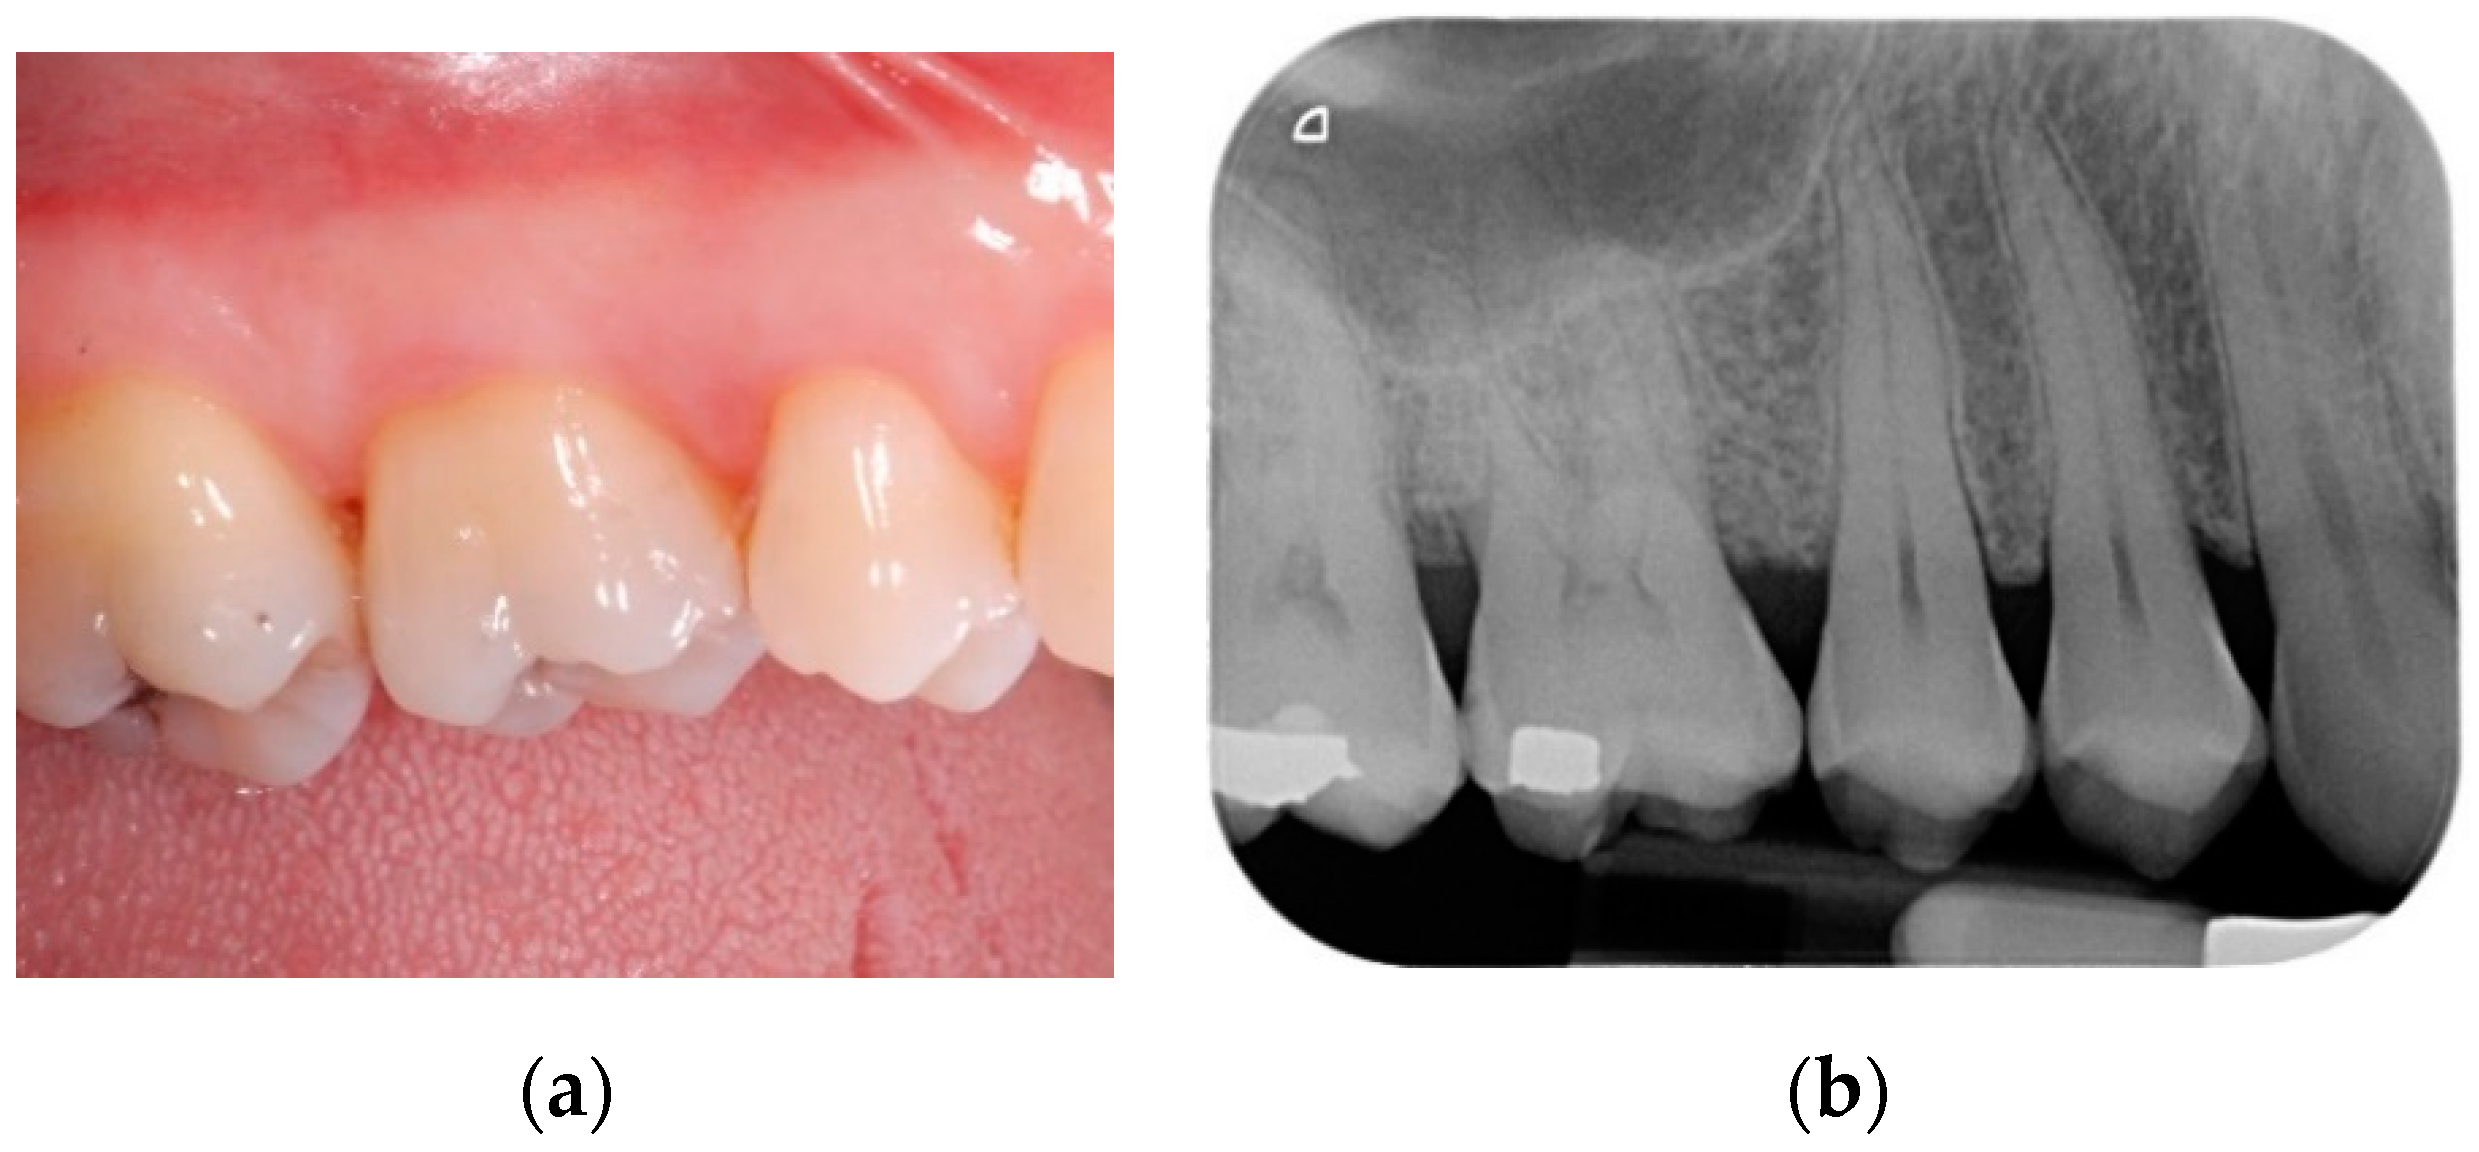

Patients were prescribed with doxyciclin 100 mg (2 tablets on the first day and then one tablet per day for 14 days) and ibuprofen 600 mg (2 tablets per day for 5 days). Three patients, who had previously reported recurrent gastritis, were also prescribed with pantoprazole 20 mg (one tablet every morning before breakfast for 10 days). Patients were instructed not to brush the treated area, but to rinse their mouth twice a day using a 0.20% chlorhexidine mouthwash, starting from the day after the surgery until suture removal. A cold diet and ice packs application were recommended for the first day after surgery. All patients were seen 7 days post-op; a second check was scheduled 2 weeks after the surgical procedure; at this time, the sutures were also removed. For the first 12 months after surgery, patients were scheduled for supportive periodontal therapy recalls every three months (Figure 3a,b).

Figure 3.

(a) Clinical view of the treated area at 12-month follow-up; (b) periapical radiograph at 12-month follow-up.